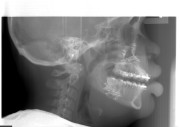

Prediction and Preoperative Workup with Model Surgery

The surgical team spends much time and energy in collaboration with the orthodontist to plan the surgery.  A joint treatment plan is devised.  The orthodontist sets up for the surgery with braces.  The surgical team then plans the surgery using xrays to predict the movements, performs the surgery on models, then fabricates acrylic splints to guide the surgical team in the operating room.